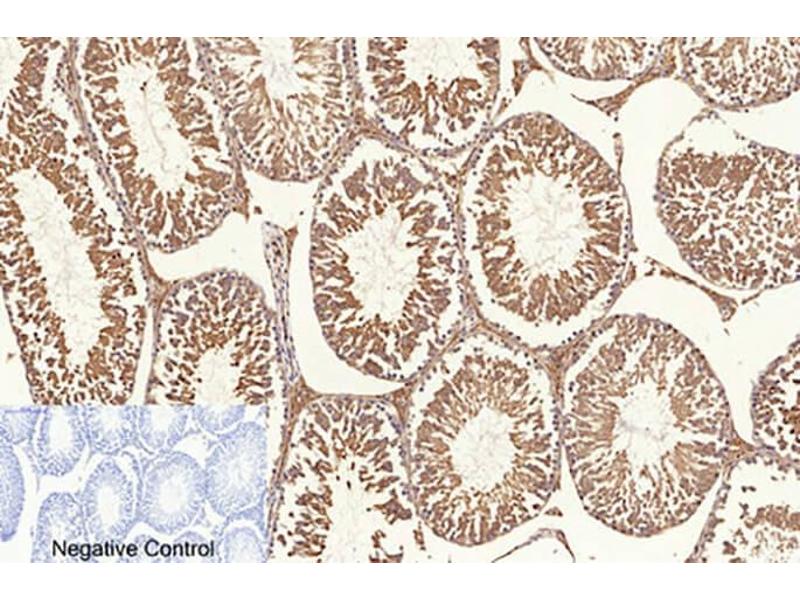

NFkBP65 Reaktivität: Human, Maus, Ratte, Rind (Kuh), Zebrafisch (Danio rerio), Kaninchen, Huhn WB, ELISA, IHC (p), FACS, IF (cc), IF (p), IHC (fro) Wirt: Kaninchen Polyclonal unconjugated

Pubmed 30 Referenzen

Produktnummer ABIN668961